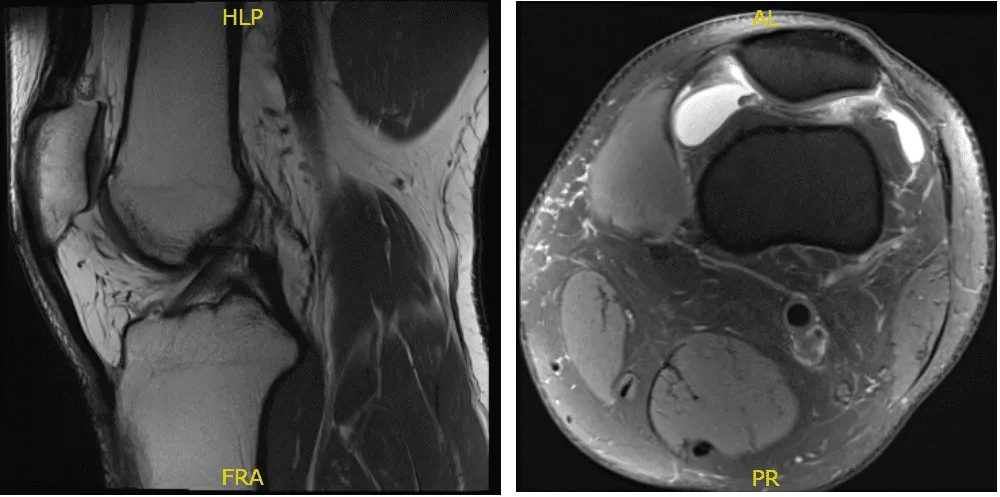

Fig. 1 Resonancia magnética de la rodilla izquierda en secciones sagital y coronal.

No hay fractura aguda ni osteonecrosis, sin embargo, hay un leve desgaste del cartílago del compartimento patelofemoral y una compleja ruptura del menisco medial que afecta al cuerpo y al cuerno posterior.

Hay una fisura cartilágica focal de grosor total sobre la troclea lateral con edema subcondral reactivo leve. La rotura muestra un componente longitudinal predominante dentro del cuerno posterior. Se observa un desgarro oblicuo horizontal adicional con deshilachado en el margen libre de los bordes.

Un edema reactivo leve está presente en la meseta tibial medial subyacente. La unión de la raíz posterior está intacta. No hay defectos de cartílago de grosor completo. Hay un derrame articular moderado. Está presente un quiste poplíteo muy pequeño. No hay cuerpos sueltos intraarticulares y sueltos.